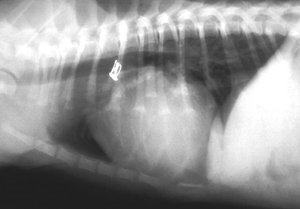

Zunächst wird der Katheter am PDA vorbei etwas weiter nach karnial geschoben und dann dort ein Angiogram (Kontraströntgenaufnahme) während einer Durchleuchtung (Fluroskopie) gemacht. Mittels Kontraströntgendarstellung kann der Durchmesser des PDA exakt gemessen, falls dies noch nicht mittels Ultraschall möglich war..

Kontrastmittelaufnahme eines PDA vor dem Verschluss:

Der PDA ist mittels der Pfeile markiert.

AO: Aorta

PA: Pulmonalarterie